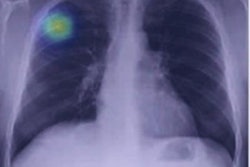

Artificial intelligence (AI) image analysis software developer Lunit has added three radiology luminaries to its advisory board.